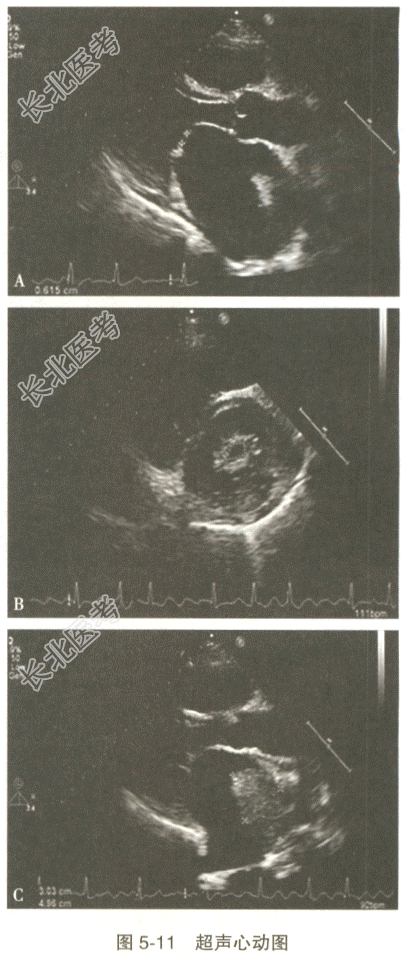

- [材料题] 患者,女性,51岁。活动后心前区不适20年。接诊医师申请超声心动图检查,测得二尖瓣瓣口面积约0.7cm²,左房顶见一大小约5.0cm×3.0cm的低回声团附着,无明显活动度。

- 多项选择题2.此患者的超声心动图见图5-11,描述的诊断信息有

A、左房扩大

B、心包积液

C、二尖瓣前后叶开口间距减小

D、二尖瓣开口面积减小

E、左房内见附壁血栓形成

F、二尖瓣增厚,回声增强